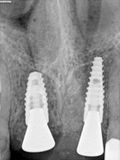

fredlibc | all galleries >> Galleries >> NSankhyan - immedaite 11 and 21 implant > R2.jpg

R2.jpg